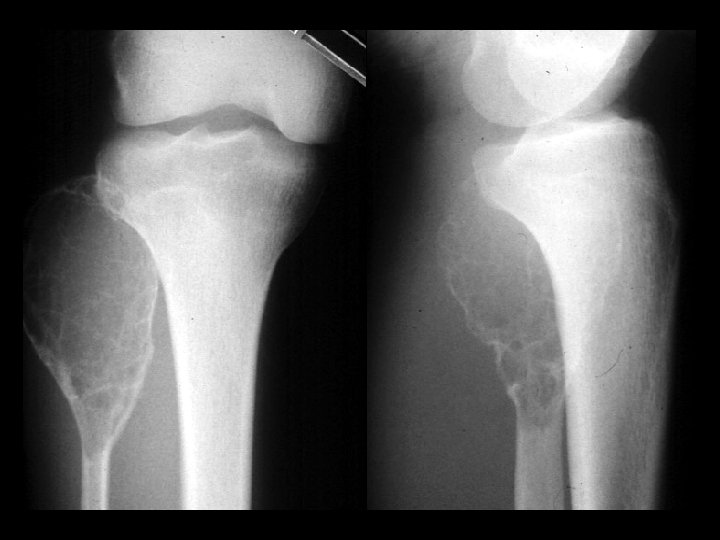

Hemangioma • Findings: – expansile lesion of the proximal tibia containing fine bony septations and a large course calcification – CT scan shows a lacey appearance • ddx: – Paget’s dz – ABC